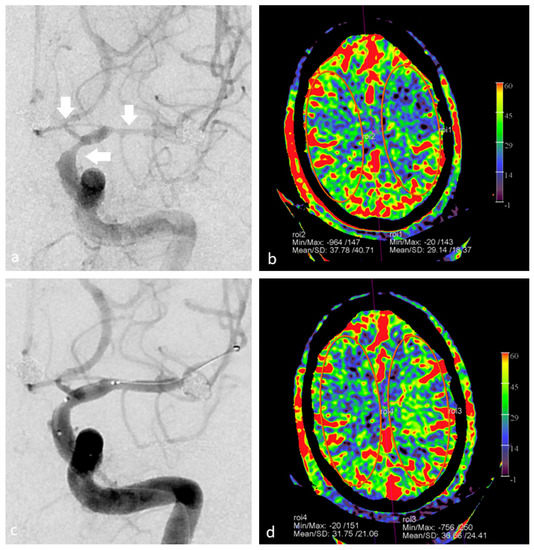

- van der Zijden, T.; Mondelaers, A.; Voormolen, M.; Yperzeele, L.; Menovsky, T. Vessel territory mapping after cerebral revascularization surgery using selective angiographic flat detector perfusion imaging. J. Integr. Neurosci. 2021, 20, 103–107. [Google Scholar] [CrossRef] [PubMed]